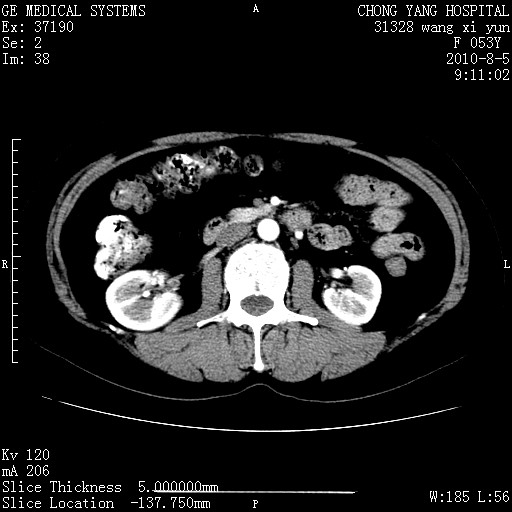

标题: CT28214:F41Y 血尿二十天,建议盆腔平扫加增强。

胆管细胞ca?

1)考虑肝左叶胆管细胞癌。2)脂肪肝。

支持胆管细胞ca。